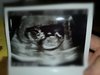

• IMG_20200220_080222.jpeg

IMG_20200220_080222.jpeg

45,3 KB · Wyświetleń: 189